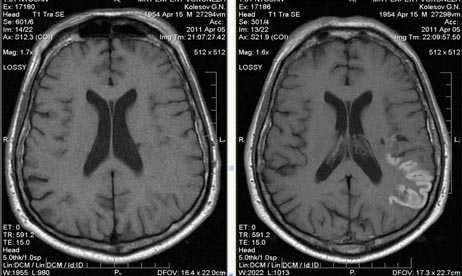

Валлеровская дегенерация вследствие инсульта в бассейне средней мозговой артерии в левом полушарии большого мозга. Р1_А1К-изображения (а, b) и Т2-ВИ в аксиальной плоскости (с). В зоне, кровоснабжаемой левой средней мозговой артерией, визуализируется кистозный дефект с глиозом (а). Определяется повышенная интенсивность сигнала от пирамидного пути в левой ножке мозга (b) и в продолговатом мозге слева (с).

- Стадия 1 (острая): До 4 нед. после повреждения на традиционных МР-изображениях не определяются патологические изменения сигнала.

- Стадия 2 (подострая): Спустя 4-14 нед. на Т2-ВИ визуализируется гипоинтенсивная зона, обусловленная начальным, а не биохимическим распадом миелина и компонентов аксона.

- Стадия 3 (хроническая): Гиперинтенсивная зона на Т2-ВИ (распад жиров и липопротеинов, вазогенный отек, глиоз).

- Стадия 4: Атрофия

- Раннее выявление возможно при использовании метода переноса намагниченности (ПМ) и диффузионно-взвешенных изображений.